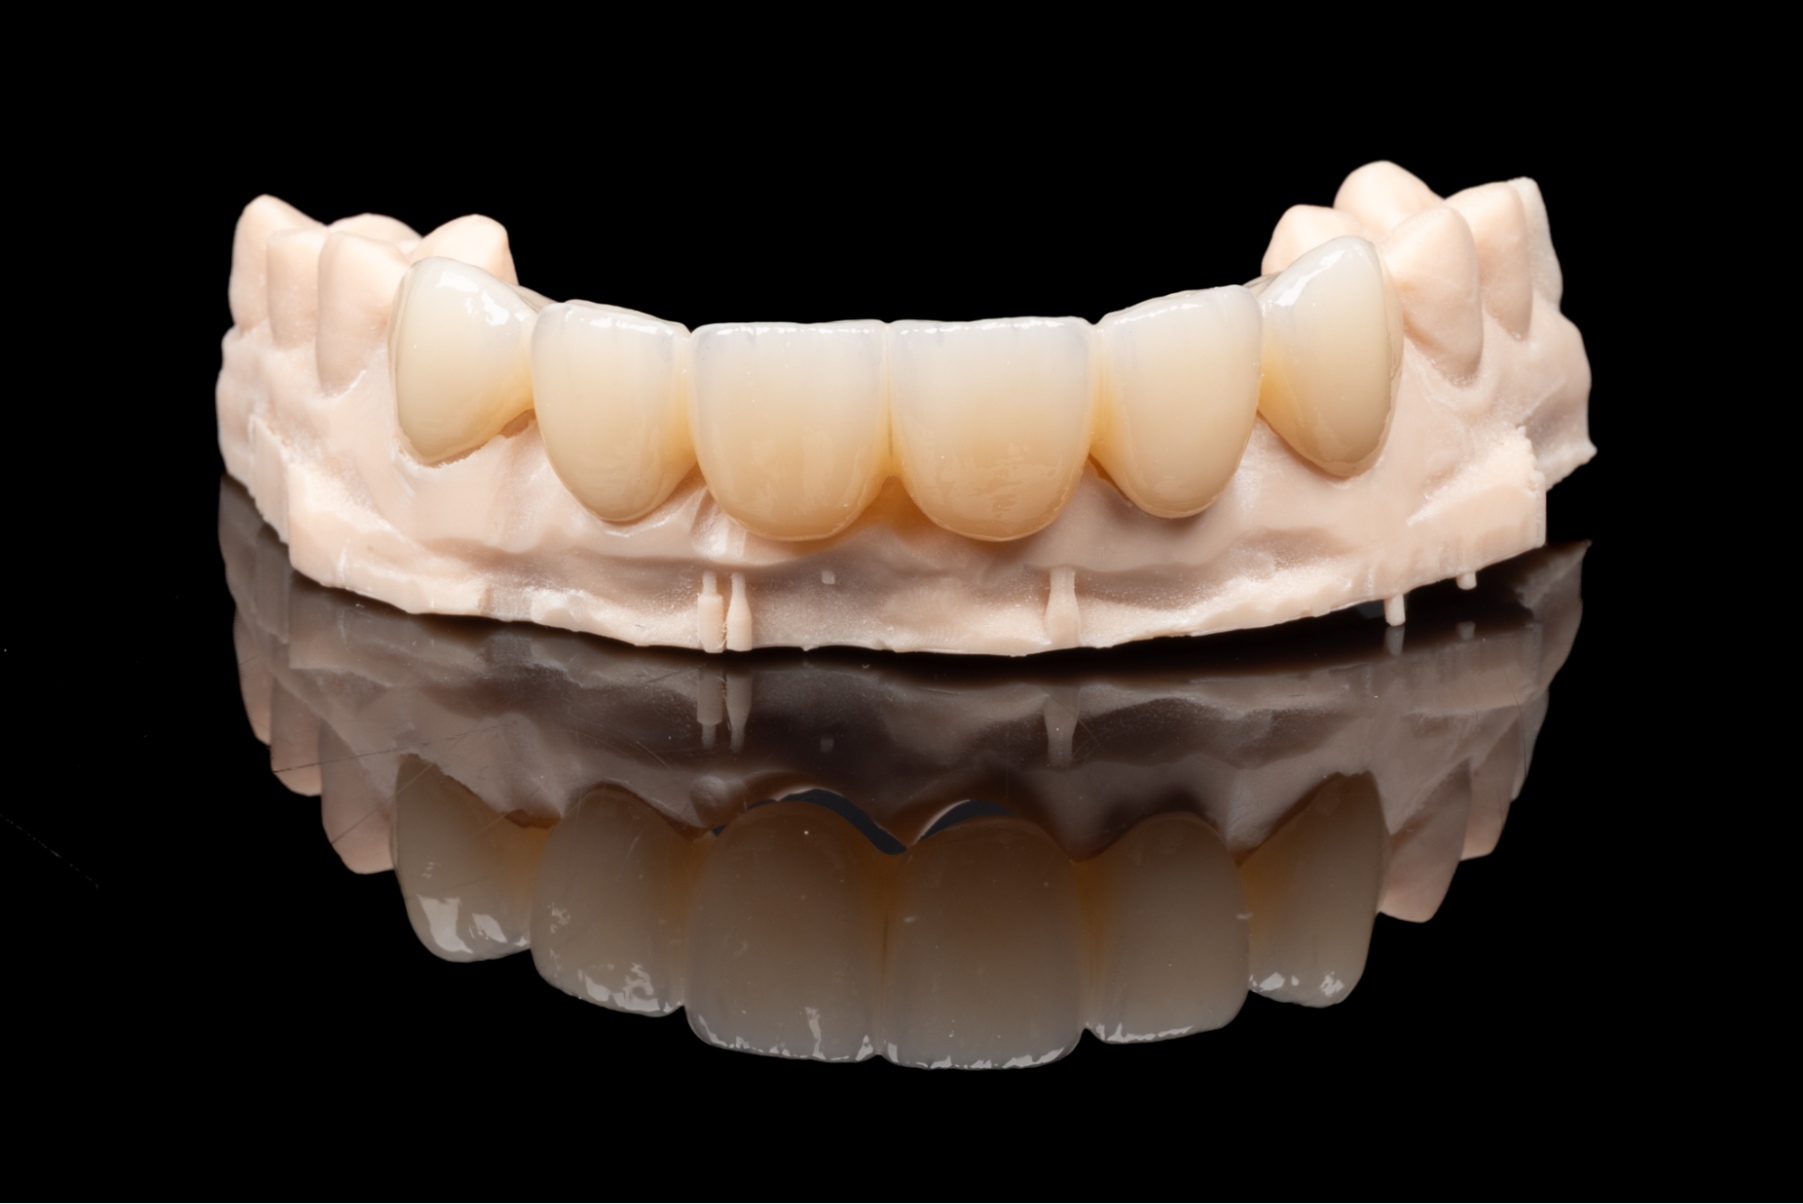

Pacjenci, którzy rozważają uzupełnienie braków w uzębieniu, często wahają się między implantem zęba a rozwiązaniami takimi jak mosty protetyczne czy protezy ruchome. Warto jednak wiedzieć, że w porównaniu z nowoczesnym leczeniem implantologicznym, zarówno most protetyczny, jak i tradycyjne protezy są rozwiązaniami kompromisowymi.

Aby uzupełnić jeden brakujący ząb za pomocą mostu protetycznego, najczęściej trzeba wykonać konstrukcję trójpunktową. Całkowity koszt takiego rozwiązania jest zbliżony do ceny implantu zęba z koroną, jednak implanty zębowe pozwalają zachować integralność sąsiednich zębów.

Oszczędność tkanek – brak ingerencji w zdrowe zęby

Założenie mostu protetycznego wymaga oszlifowania sąsiednich, często zupełnie zdrowych zębów, które stają się filarami konstrukcji. Wszczepienie implantu pozwala tego uniknąć -to uzupełnienie braków bez ingerencji w strukturę sąsiednich zębów.

Higiena i trwałość

Pojedynczy implant zęba z koroną funkcjonuje jak naturalny ząb i jest łatwy w oczyszczaniu. Most protetyczny, jako konstrukcja zespolona, utrudnia higienę, co może prowadzić do stanów zapalnych dziąseł i skrócenia jego żywotności.